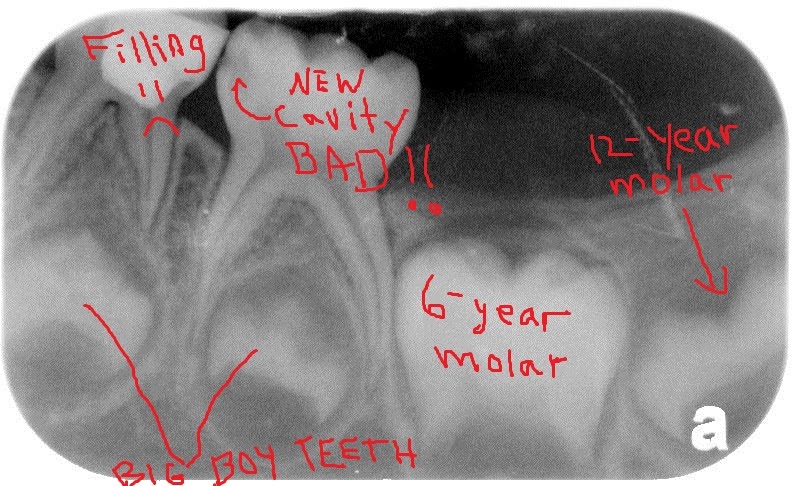

An Attempt to Cure Tooth Decay Xray Proof of my Cavity . This quick guide shows you some of what we see and what we are looking for.

Xray review (teeth, dentist, cavity, filling) Dental . If positioning is not precise, a poor image can result.

Xray review (teeth, dentist, cavity, filling) Dental . If positioning is not precise, a poor image can result.